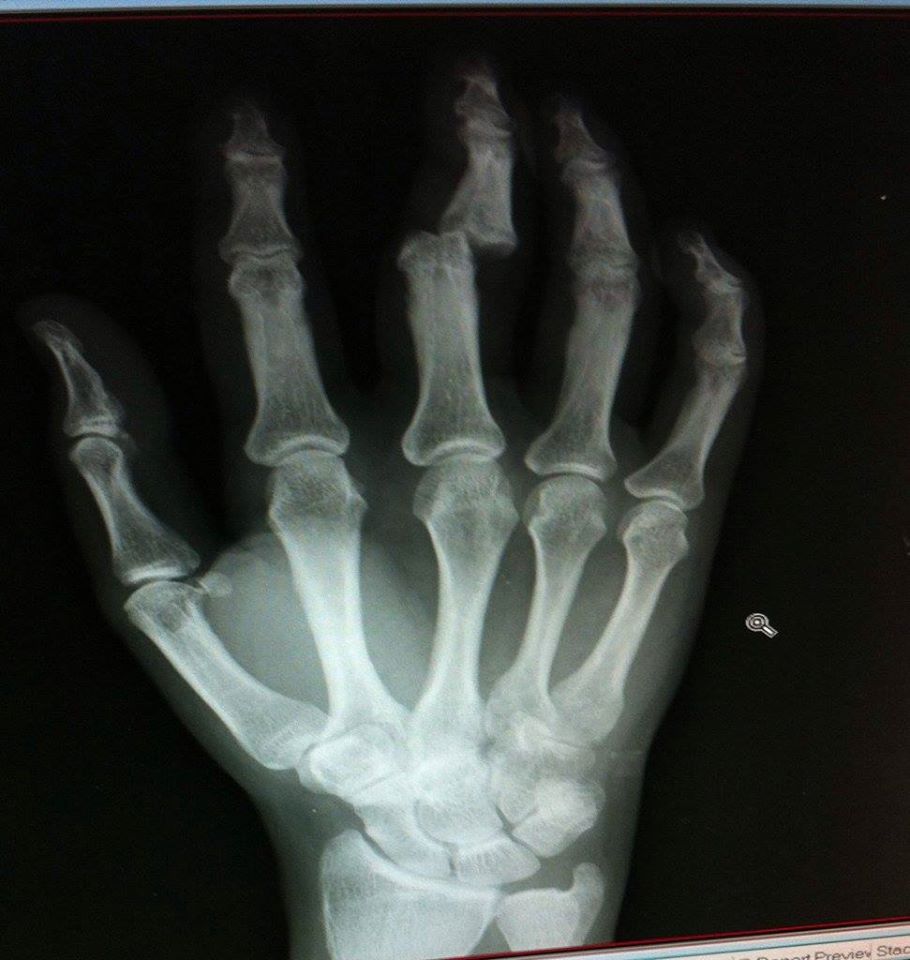

Ich gehe normalerweise am morgigen Tag in die Mikve für ein rituelles Bad. Dieses Jahr wird daraus nichts, denn meine Finger der rechten Hand sind mit einem Verband fixiert. Ich hatte heute einen Unfall mit dem Fahrrad und habe mir den rechten Mittelfinger ausgekugelt.